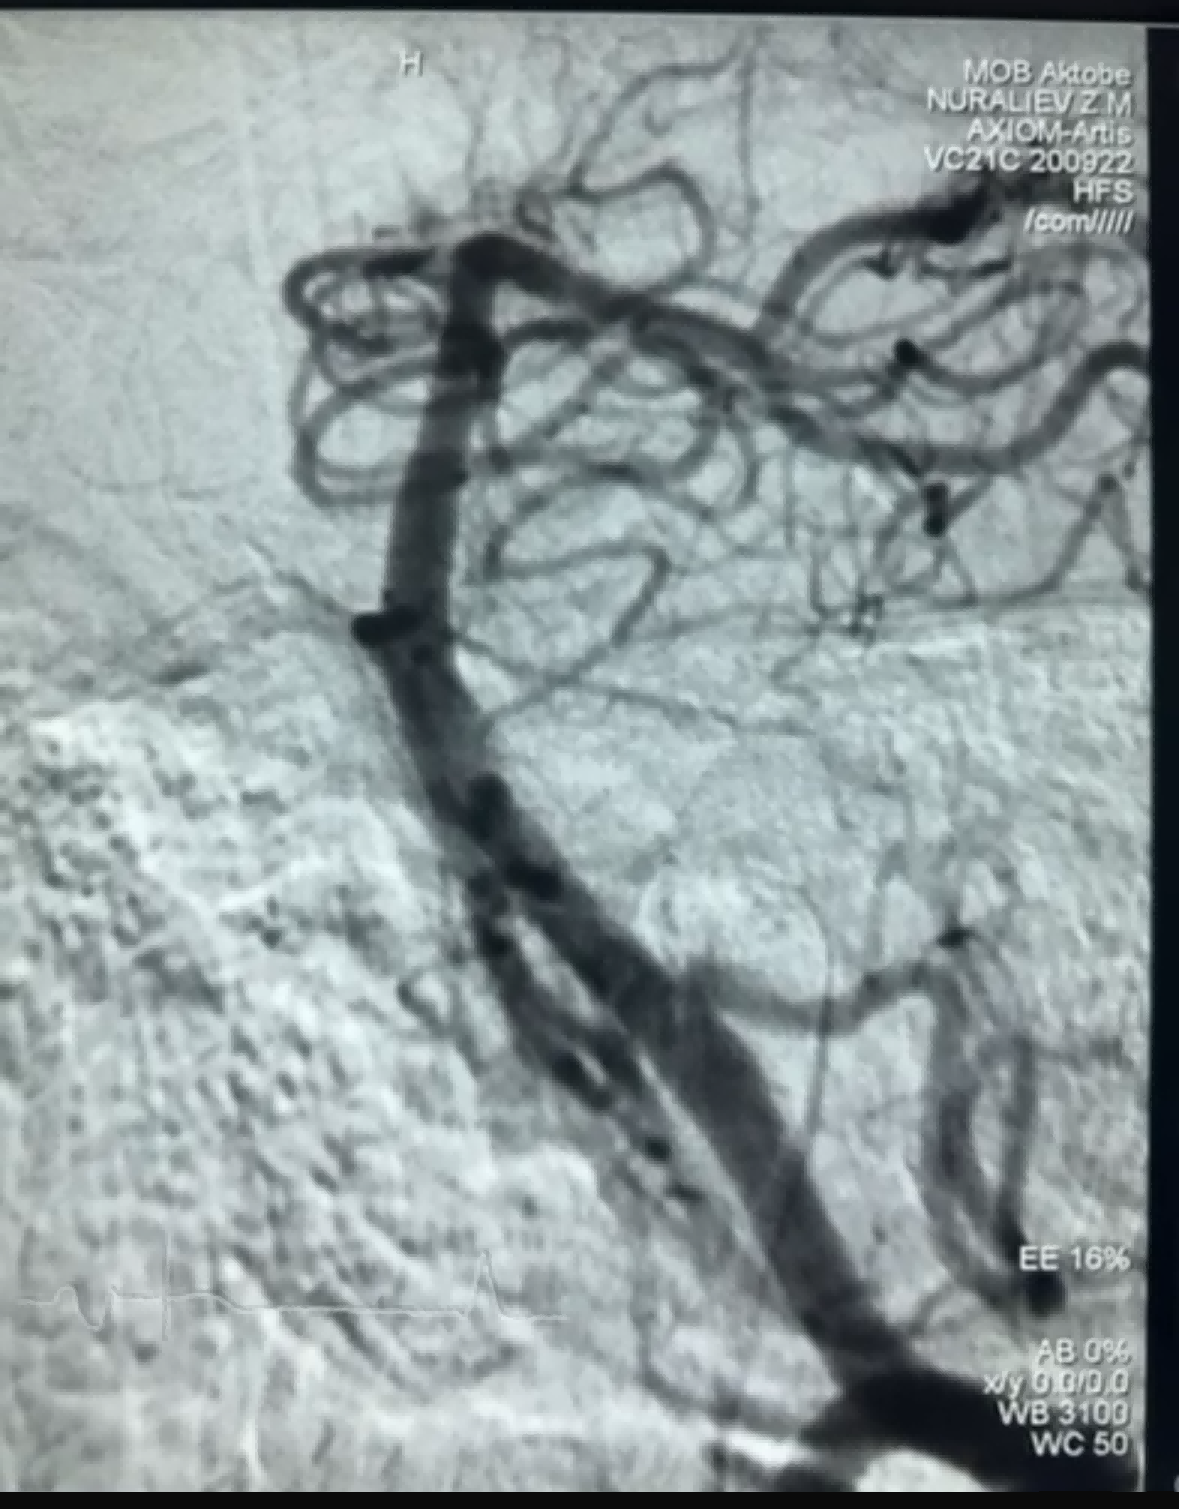

A közelmúltban volt egy sikeres thrombectomiás eset a NeuroSafe Medical Co., Ltd. Dredger Stent Retrieverével. A Dredger Stent Retriever nem invazív lágy hegye nagymértékben csökkenti az intima károsodásának kockázatát, és egyedülálló, speciális alakú lyukkal rendelkezik. olyan kialakítás, amely elsősorban a résváltozások rögzítésével rögzíti a vérrögöket.